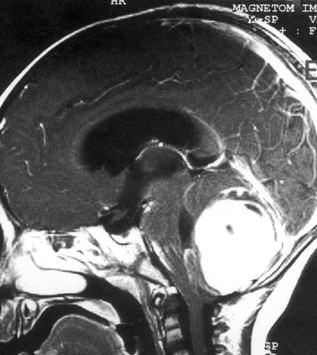

问题 病历摘要:??患儿男性,11岁。半年前开始出现行走不稳,常无故跌倒。半月前出现发作性剧烈头痛,伴恶心呕吐。体检:T36℃,P100次/分,R22次/分,BP100/60mmHg,神清,言语较缓慢,双眼外展约不及边,双眼侧视时有小幅度水平眼震。四肢肌力正常,右上肢肌张力较低,坐位姿势不稳,常不自主摇晃,双上肢指鼻不准,行走蹒跚步态,足距扩大,身前倾。 初步诊断考虑哪些疾病?提示:患儿行头颅?MR检查(见图)

选项 A.室管膜瘤 B.转移瘤 C.淋巴瘤 D.髓母细胞瘤 E.血管网状细胞瘤 F.星形细胞瘤 G.脉络丛乳头状瘤 H.多形胶质母细胞瘤

答案 ADFG